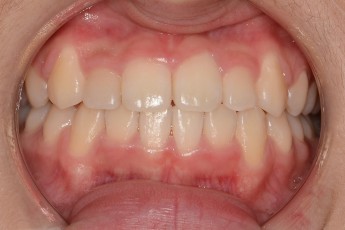

BEFORE & AFTER